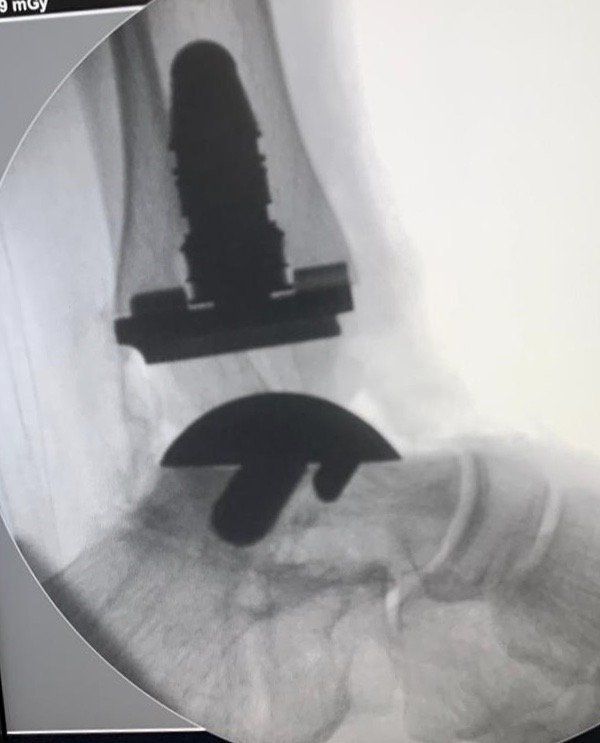

Além da participação como congressista, o Dr Rogério Bitar enviou um e-Poster referente ao estudo do arco de movimento obtido no intra-operatório após a realização da Artroplastia Total de Tornozelo. Este estudo foi proposto pelo Dr Rogério Bitar durante o seu estágio no Hospital for Special Surgery de NY em 2019.

19/09 e 21/09/20: Realizado mais 2 próteses totais de tornozelo em Ribeirão Preto para tratamento da osteoartrose avançada do tornozelo. Tivemos o prazer em receber 3 colegas de fora da cidade (Araçatuba, Limeira e Indaiatuba) que vieram acompanhar as cirurgias com o intuito de oferecer esta alternativa de tratamento para os seus pacientes.

05/12/2020: As fraturas do tornozelo podem levar a um processo degenerativo chamado de artrose ou osteoartrose. O estágio final desta doença se caracteriza por dor e limitação da marcha. Uma das soluções de tratamento é a Artroplastia Total do Tornozelo ou prótese de tornozelo, que tem o objetivo de eliminar a dor e devolver a função. Este sábado podemos realizar mais uma prótese de tornozelo para tratamento de um quadro de osteoartrose pós-traumática.

Paciente do Paraguai foi submetido a Artroplastia Total do Tornozelo neste último sábado no Hospital Viver de Ribeirão Preto com o Dr Rogério Bitar e o Dr Alexandre Leme Godoy dos Santos. O paciente optou pela artroplastia após ter passado por diversos médicos que sugeriram fazer a fusão do tornozelo. O paciente segue em recuperação.